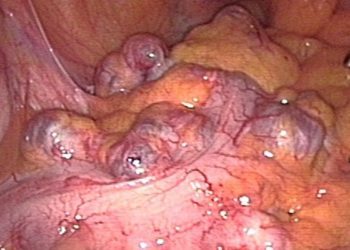

Fecal microbiota transplantation may be more effective than vancomycin in treating primary C. difficile infection

1. In this randomized controlled trial, a higher proportion of patients who underwent fecal microbiota transplantation achieved clinical cure of ...